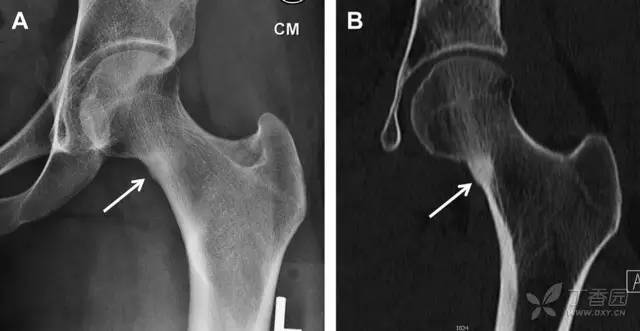

股骨颈骨折常发生在老年人,头下型骨折最常见,但是当股骨外旋或有明显的关节炎骨赘形成时,骨折较难发现。此外,肥胖和骨量减少增加髋部 X 片诊断难度,所以需格外注意。

因骨结构重叠影响,股骨转子骨折发生轻度移位时亦很难发现,加做一个不同角度的 X 线片有助于诊断(图 7)。

图 7 摔倒后股骨大转子骨折。A 正位片初步检查未发现明显骨折,进一步检查发现大转子上方皮质中断(箭头)。B 蛙式侧位片示骨折分离,尤其是后方(箭头)。初步检查时忽视了这一点,是因为股骨颈未能充分显示